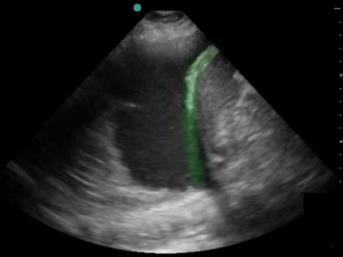

膈膜高亮图像

高亮区域:隔膜